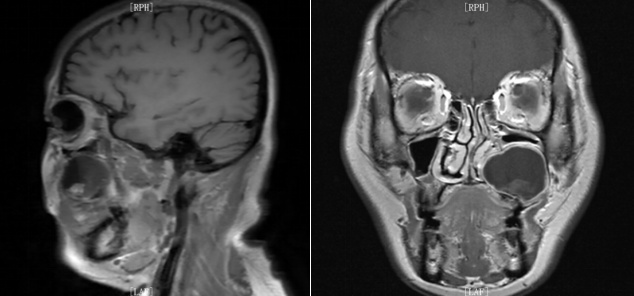

术前影像学检查:MRI检查及CT检查示左侧上颌骨内囊肿样病变,直径约4.0厘米,周围骨质呈压迫性吸收,左侧上颌窦腔被压迫缩小。